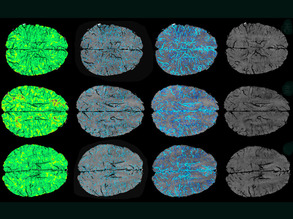

Mind Map

11